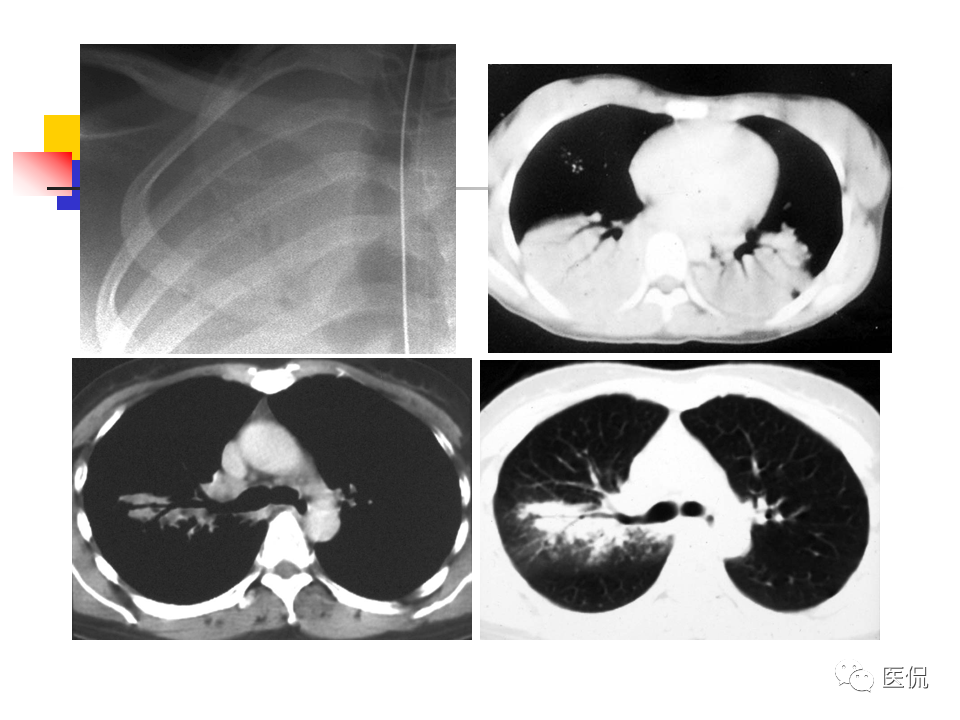

大叶性肺炎|大叶性肺炎的影像诊断

大叶性肺炎影像诊断